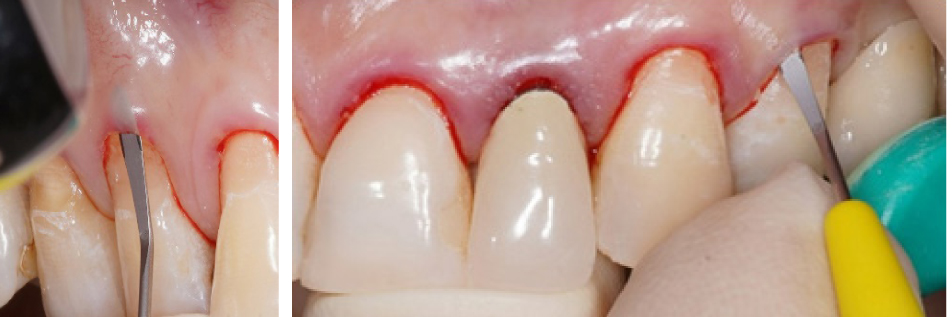

Вначале проводилась антисептическая обработка полости рта 0,05%-м раствором хлоргексидина биглюконата, аппликационная и инфильтрационная анестезии. Затем выполнялись разрезы в области десневой борозды (сулькулярные) через каждую зону рецессии микрохирургическим лезвием с сохранением кончиков десневых сосочков (рис. 2), отслаивание полнослойных лоскутов с помощью микрохирургического распатора. Далее производился забор свободного десневого трансплантата с неба с последующей его внеротовой деэпителизацией и наложением на зону забора параллельных и перекрестных горизонтальных обвивных швов (рис. 3). Позиционирование и фиксация трансплантата в принимающем ложе, ушивание раневой поверхности швами Аллена (рис. 4). Даны рекомендации по послеоперационному ведению: полоскания 0,05%-м раствором хлоргексидина биглюконата 2 раза в день в течение 2 недель, назначены противовоспалительные и обезболивающие лекарственные препараты (НПВС). Повторная явка через день. Швы снимались на 7–10-е сутки. Контрольные осмотры проводились через 3 и 6 месяцев, 1, 2 и 3 года соответственно, оценивалось состояние мягких тканей в области хирургического вмешательства и степень закрытия рецессий десневого края.

Рис. 2. Внутрибороздковые разрезы микрохирургическим лезвием